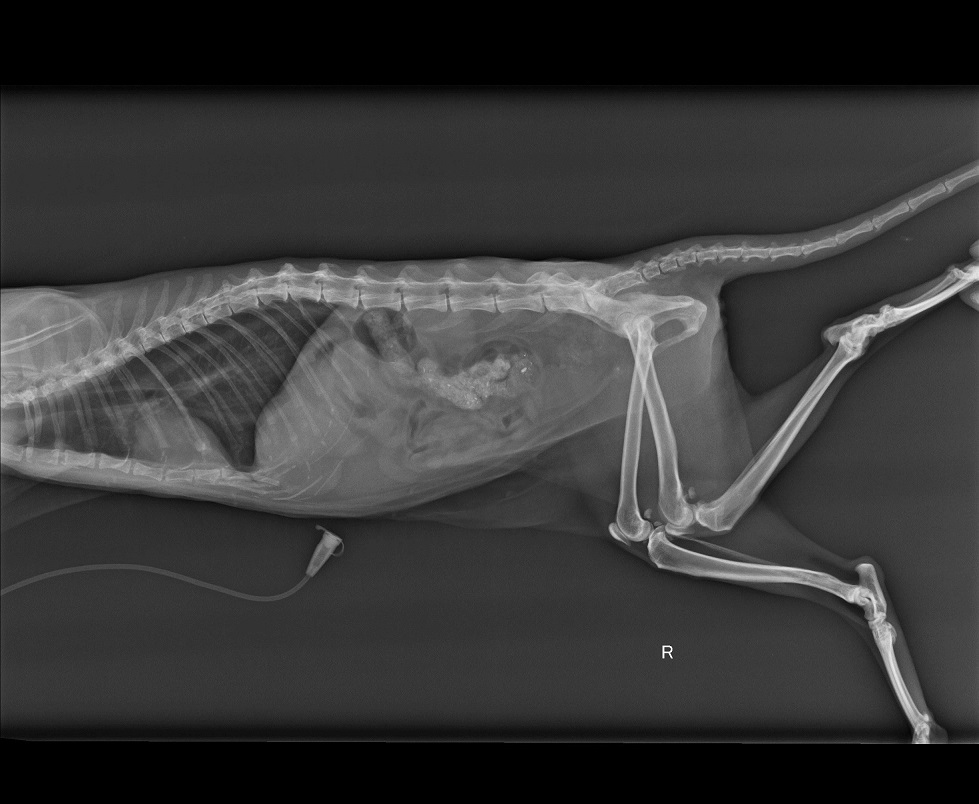

當下的小黑幾乎沒有抵抗的力氣,應該是多天沒吃飯造成的,趕緊送醫後,發現有嚴重貧血•腎衰•以及嚴重的骨盆骨折.......

聽到檢查結果,愛媽快要嚇傻了。因為血檢結果貧血很嚴重,先處理這部分,等身體狀況好些後再處理接下來的問題。動物近況說明: 經過了半個月的治療,小黑狀況有較穩定,但沒很大的起色。